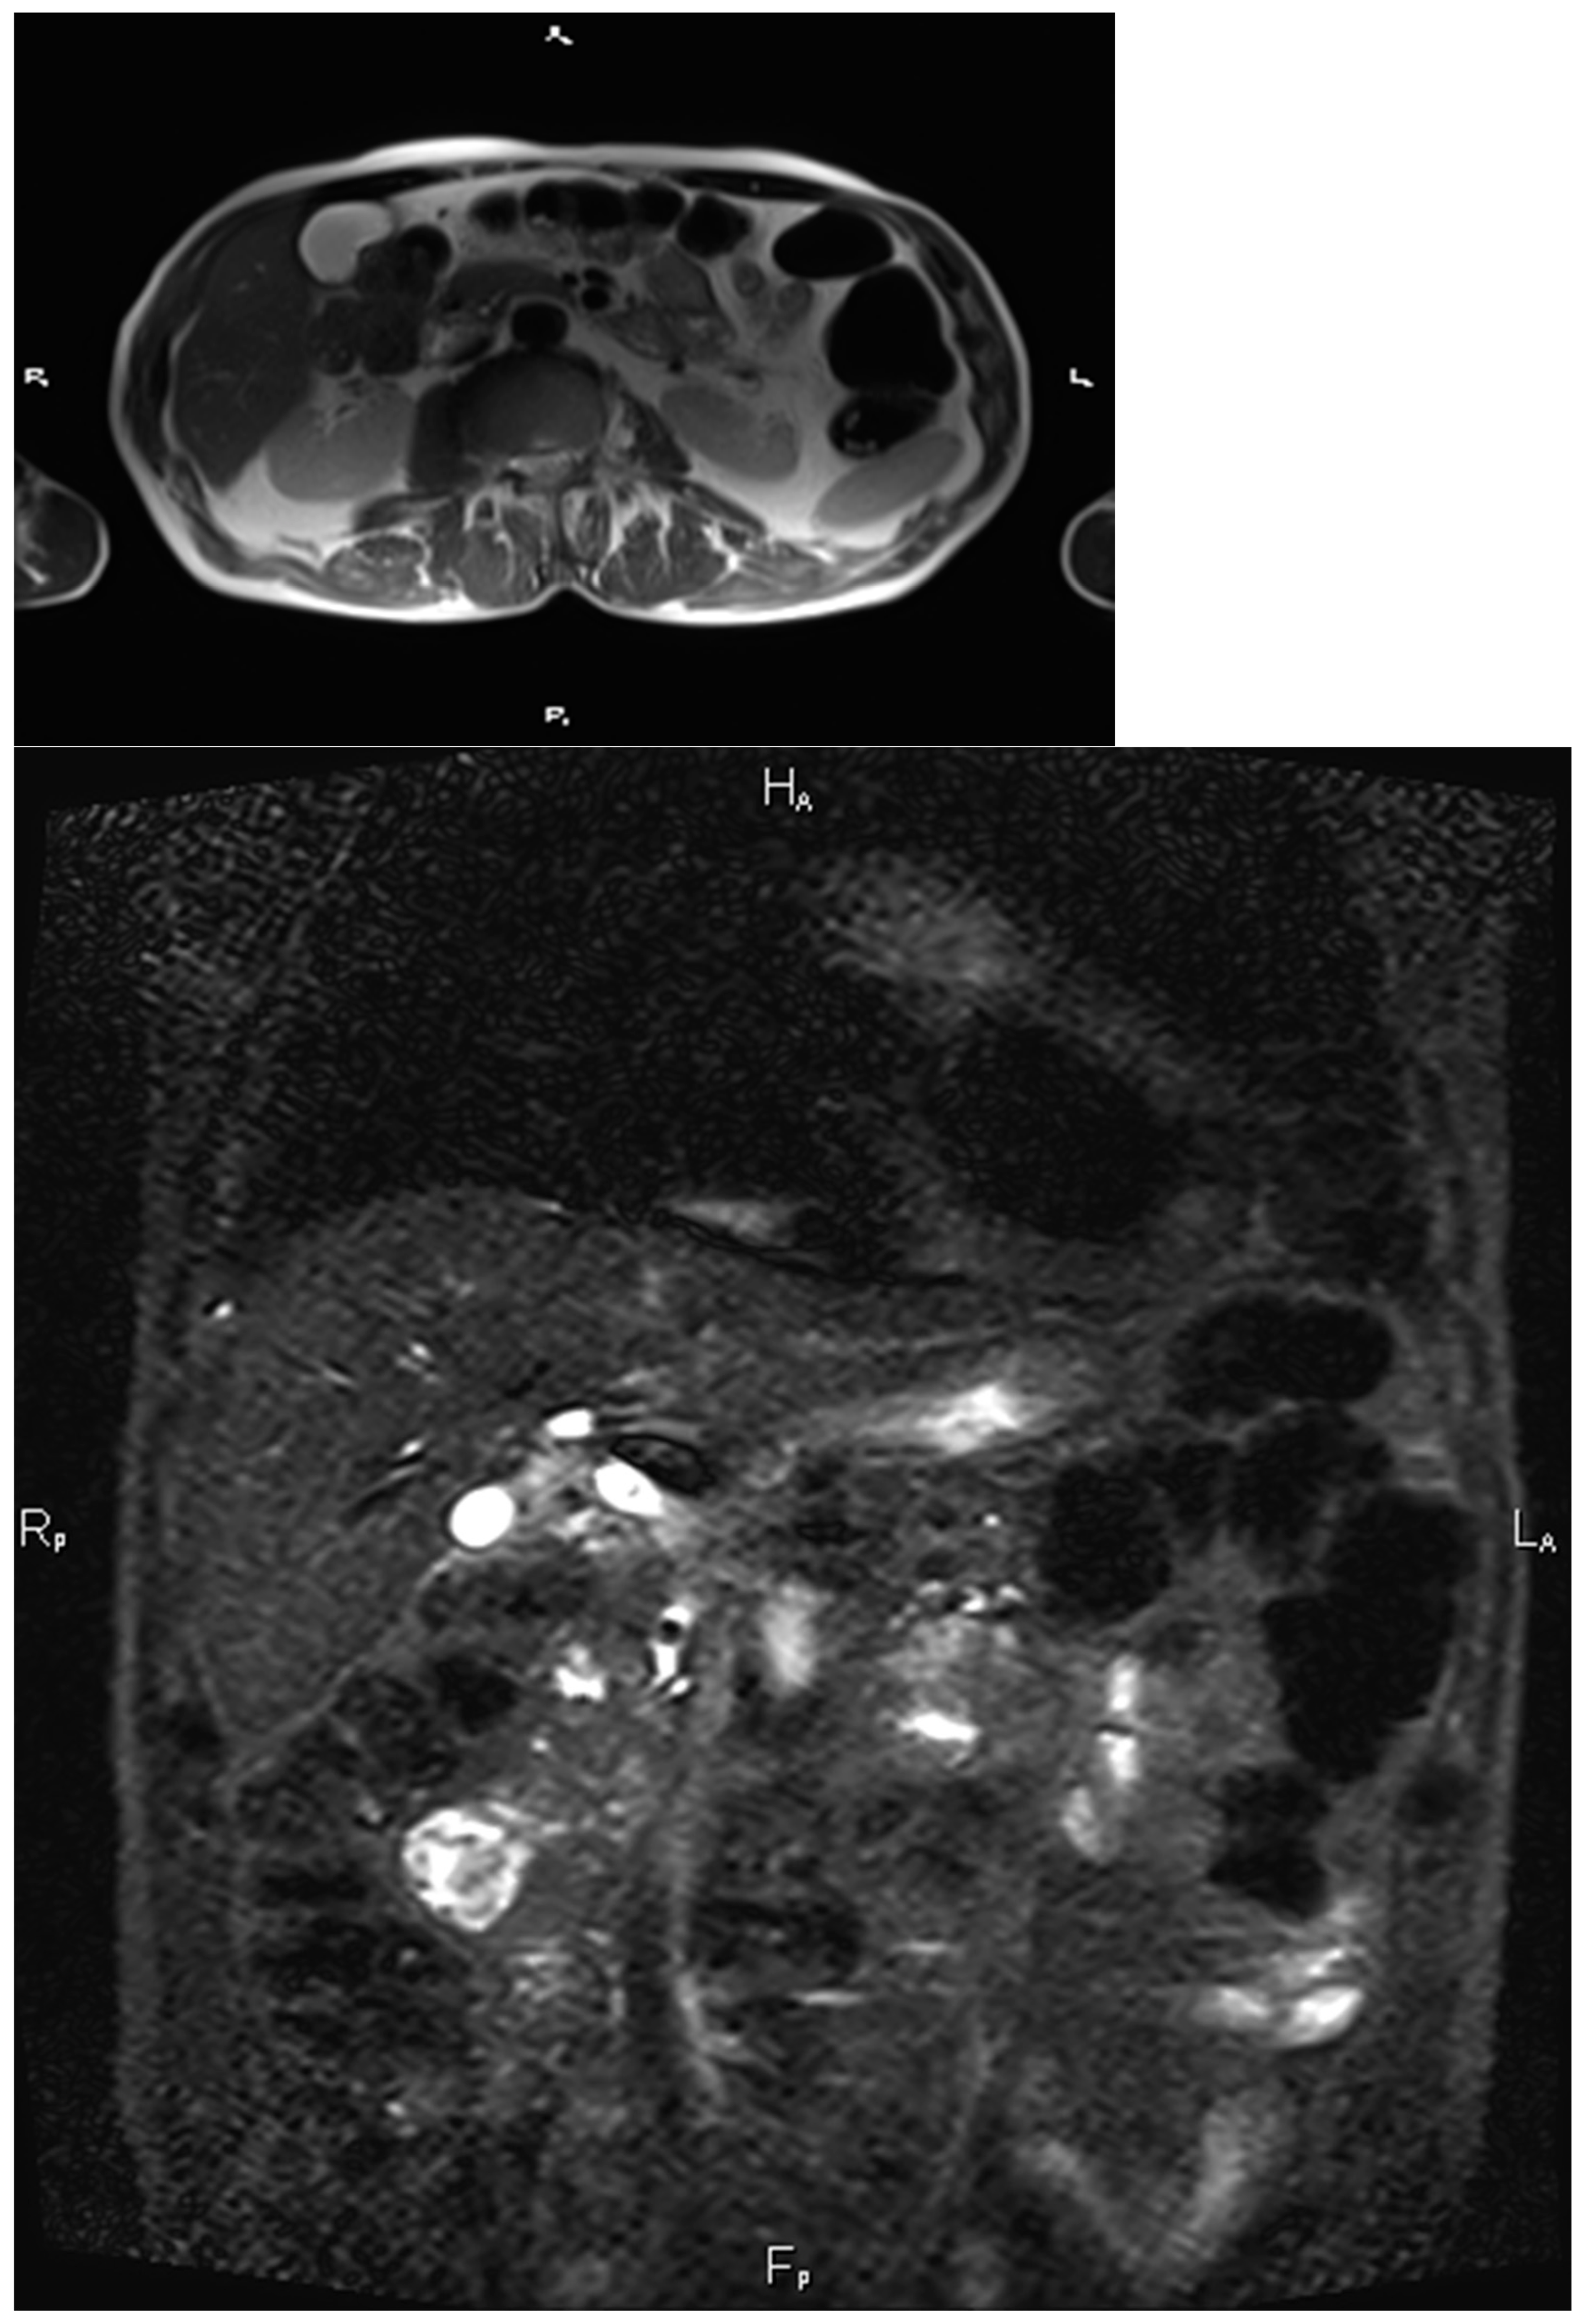

Complications

5. Diagnosis

- Renzulli, M.; Caretti, D.; Pettinari, I.; Biselli, M.; Brocchi, S.; Sergenti, A.; Brandi, N.; Golfieri, R. Optimization of pineapple juice amount used as a negative oral contrast agent in magnetic resonance cholangiopancreatography. Sci. Rep. 2022, 12, 531. [Google Scholar] [CrossRef] [PubMed]